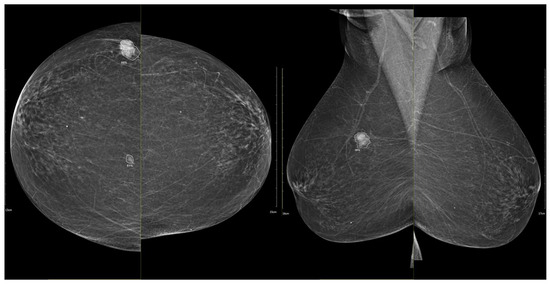

Figure 5. (a) Low-energy CC and MLO views reveal a focal asymmetry with associated suspicious microcalcifications and retraction of Cooper’s ligaments in the upper outer quadrant of the left breast. An oval, well-circumscribed mass with circumscribed margins is seen at the junction of the lower quadrants of the right breast. (b) Recombined contrast-enhanced images (CC and MLO views) demonstrate a large inhomogeneous enhancing area, with two closely situated, partially marginated masses in the upper outer quadrant of the left breast. The right breast lesion shows homogeneous early enhancement without washout on delayed images—findings suggestive of a benign lymph node or fibroadenoma. In the visualized portions of both axillae, no pathologically enhancing lymph nodes are identified. Histopathological analysis confirmed a HER2-enriched breast carcinoma.

Figure 6. (a) Standard CC and MLO images reveal a relatively well-circumscribed, round to oval mass in the left retroareolar region, without suspicious calcifications. The right breast appears unremarkable. (b) On recombined contrast-enhanced images (CC and MLO), the same lesion demonstrates rim enhancement with irregular, heterogeneous internal contrast uptake. The enhancement shows early rapid contrast accumulation—a pattern that raises concern for malignancy. In the visualized portions of both axillae, no pathologically enhancing lymph nodes are identified. Histopathological examination confirmed the diagnosis of triple-negative breast carcinoma.